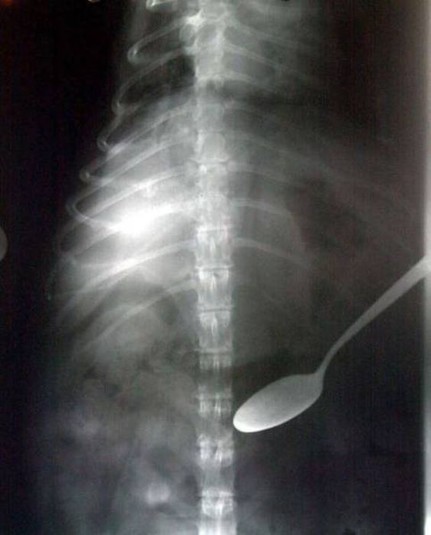

Предметы, которые не очень хочется видеть внутри себя

Под рентгеновскими лучами порой видны не только внутренние органы и кости, но и инородные тела, попавшие в организм

Истории попадания этих предметов в организм могут быть самыми невероятными и запутанными, но больше всего медиков интересует процесс их извлечения, впрочем, в этом заинтересованы и сами пациенты, допустившие нечто подобное со своим телом.